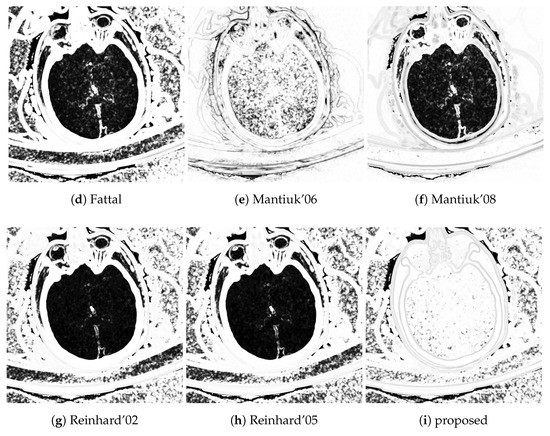

TMQI offers structural similarity maps at various resolution levels. Figure 9 shows the finest resolution structural similarity maps of the different tone mapping operators using the head CT example. The advantage of the proposed method is that it has better structural similarity for medium densities, e.g., white and gray matter in the brain, than the alternative methods which mostly perform well outside of the skull.

Figure 9.

Structural similarity map for the head CT example. Brighter shades belong to higher local structural similarity (white = 1.0, black = 0.0).

Traditional TMOs offer dynamic range compression with low noise but good local contrast. These operators perform well for selected sub-problems, usually either for low densities (lung) or for high densities (bones). The challenge for these algorithms is to reproduce good local contrast for medium densities (soft tissues) where the contrast is already low in the source. This situation is common in head CTs where the soft tissue contrast is poor.